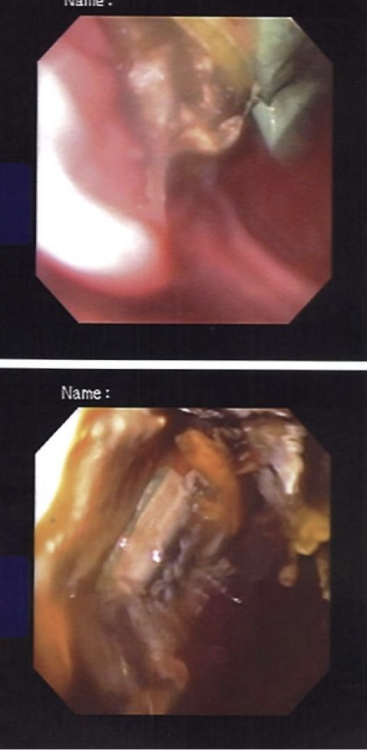

試験的に内視鏡検査を行い胃の中を確認したところ、

多数のペースト状おやつの袋が胃内に残存していることが判明しました。

内視鏡検査画像

内視鏡下での摘出を試みましたが、すべてを安全に回収することは困難と判断し、

「胃切開術(胃を切開して異物を摘出する手術)」を行うこととなりました。